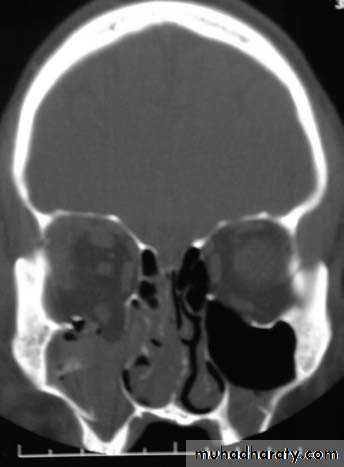

RADIOGRAPHIC EXAMINATION

Computed TomographyCT is the gold standard for radiographic evaluation of zygomatic fractures. Axial and coronal images are obtained to define fracture patterns, degree of displacement, and comminution and to evaluate the orbital soft tissues.